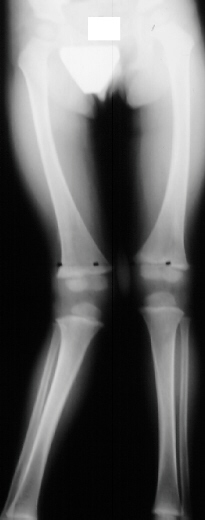

X-RAY: Standing AP films of the bilateral lower extremities revealed a tibial femoral angle of 17 degrees of the right knee in March 1996 and a progression to 27 degrees by July 1996. Neutral alignment of the left knee was noted.

No osseous pathology was seen on radiograph.